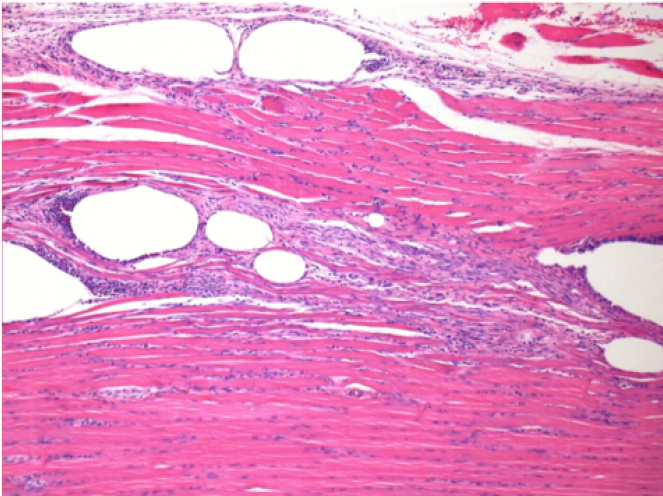

1 month after Endopeel Injection 0.1ml in the right pretibial muscle.

What is seen in black on the pictures is not a necrosis like could imagine some scientifics !

In fact, 4 conclusions have to be taken in consideration